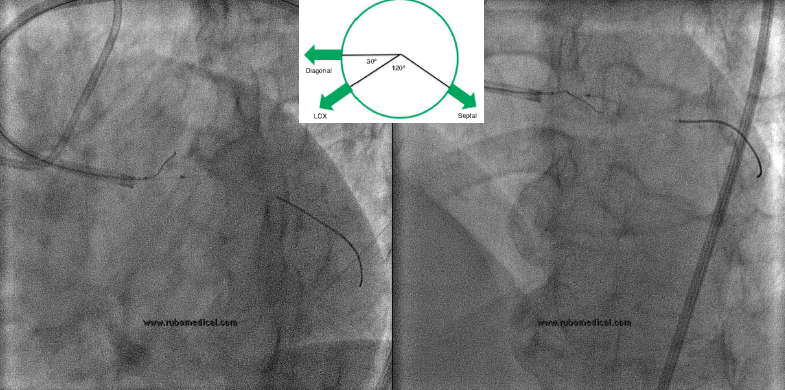

IVUS in diagonal or in OM?

IVUS in Side branch

LCX coming in

Ostial LAD

结合IVUS图像确认穿刺点及穿刺方向

MC+ pilot 150, crossed